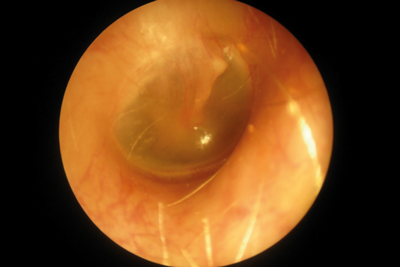

Nikon P5100 - otoscopy image.

Digital camera + adapters

Type: Nikon P5100 Compact (12 megapixel) (requires endoscope + light source)

Cost: Nikon Ur-e20 adapter = £49 Storz 590-70 coupling = £172

Image quality: 80%

Field of view: 100%

Ease of use: 95%

Comments: This camera model is no longer available but was included in the test for comparative purposes as it was already in use in our department. Adapters can be purchased for most digital cameras and offer an alternative to bespoke products. Digital cameras provide very good image quality and are exceptionally easy to use due to ergonomic and intuitive camera controls.